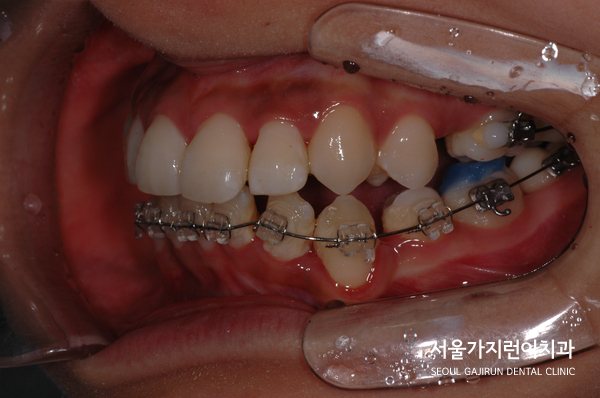

환자분의 경우 상악앞니가 많이 돌출된 케이스에 하악 앞니가 안쪽으로 기울어져 있는 상태였는데요. 전체적으로 치열이 많이 비뚤어져 있었기 때문에 앞니로 음식을 끊어먹는 것에 어려움을 겪고 계셨습니다. 특히 입을 다물려 해도 앞니의 돌출감 때문에 잘 다물어지지 않았고 중심선도 맞지 않아 여러 불편함을 안고 계셨는데요.

상악앞니의 돌출감이 심했기 때문에 상악의 경우 설측교정장치를 이용하고 하악의 경우 순측으로 진행하는 콤비교정을 진행했습니다. 돌출입 교정시에 이미 튀어나온 입에 튀어나오는 장치를 착용할 경우 교정기간 내내 입이 더 튀어나와보이는 증상으로 스트레스를 호소할 수 있었는데요. 이렇게 설측으로 진행하고 콤비교정으로 진행하면 합리적으로 치아교정을 마무리할 수 있습니다.

환자분의 경우 충분한 치아이동 공간이 필요했기 때문에 상하악 발치를 모두 진행하였으며 씹는 면을 맞게 조정하고 발치공간을 닫아나가는 시간이 필요했는데요. 2년 정도 소요된 이후에 돌출감이 사라지고 치아들이 제 자리를 찾아간 것을 확인할 수 있었습니다.

환자분이 진행한 치아교정은 설측탄댐교정방식이었는데요. 치아의 쓰러짐 없이 안정적으로 자리를 찾았고 미니스크류를 더해 정교한 컨트롤이 진행되었습니다. 사진을 보면 중심선도 맞고 뻐드러진 돌출감도 많이 해소되었는데요. 전체적인 치열이 잘 정돈된 것을 확인할 수 있었습니다.